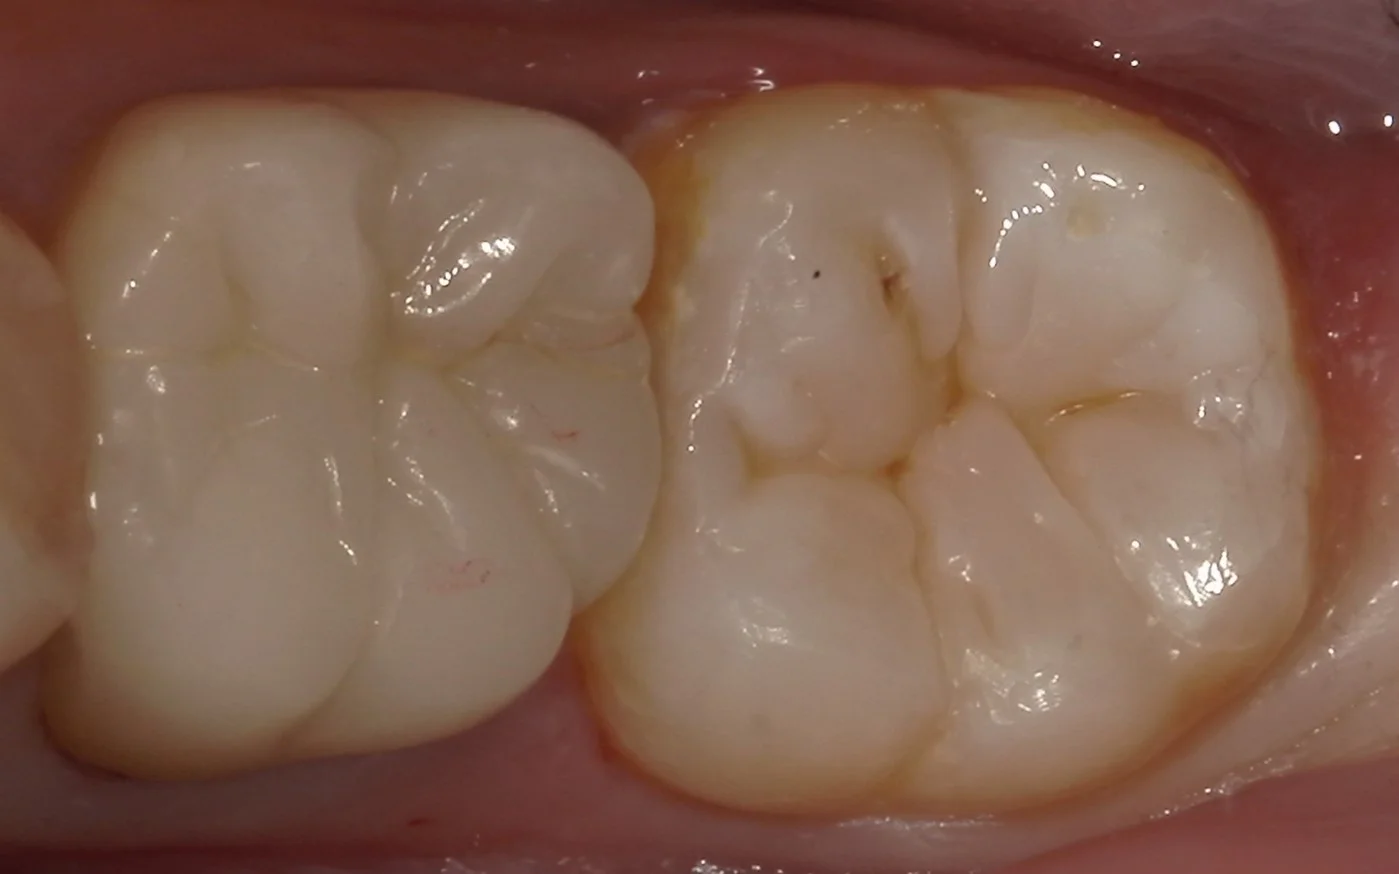

詰め終わって噛み合わせの調整も終わった写真がこちらになります。

手前の歯がオールセラミックですが、形態を似せた方が違和感が少ないので、

Y字型のデザインで仕上げました。

溝の部分のステイン(着色)部分はこれまた手前の歯に合わせるために薄めに仕上げています。

見た目はもちろんですが、歯の表面に存在するエナメル質の大部分を温存することが出来たので、この治療は非常に長持ちさせることが出来ると思いますヽ(゚∀゚)ノ パッ☆